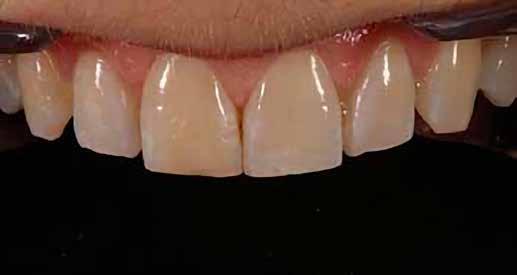

Esetpélda árnyalatokkal

Egy páciens elégedetlen volt a 8. fog incisofaciális felszínén lévő kéthetes restaurációval, mert úgy gondolta, hogy a központi metszőfogak nem illeszkednek egymáshoz. A vizsgálat során megállapították, hogy bár az egyszínű kompozit valóban megegyezett a fog alapszínével, további színre (árnyalatra) volt szükség a szomszédos fog utánzásához (4. ábra).

A fogakat nehéz latexmentes gumidámmal (Isodam, 4D Rubber) izolálták. A meglévő kompozitot eltávolítottuk; egy kromatikus mikrotöltésű kompozitot helyeztünk fel, és egy fehér színt (Creating Color, Cosmedent) vittünk fel egy #8-as K-résszel, vízszintes mozgással, hogy a vízszintes mintázatot lemásoljuk (5. ábra), ezután egy akromatikus mikrotöltésű kompozitot adtak hozzá. A 6. ábra az azonnali posztoperatív eredményt mutatja, a 7. ábra pedig a négyéves utóvizsgálatot, amely a mikrotöltött kompozit megmaradt fényét mutatja.